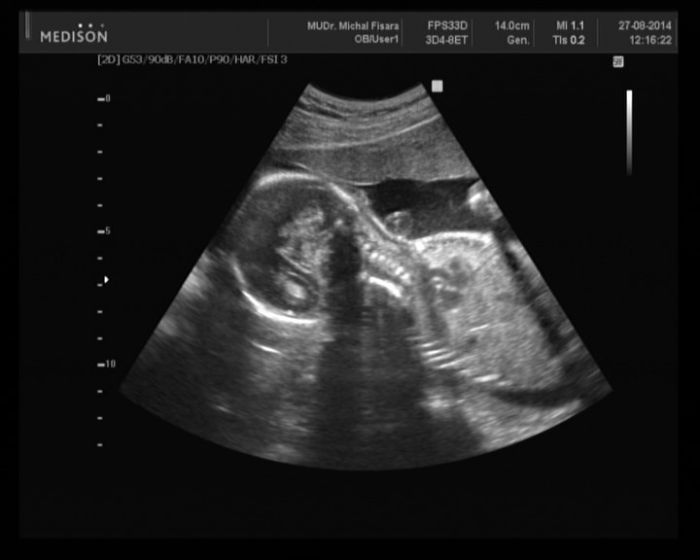

Tak dnešní veliký UTZ za námi vše v pořádku a pan doktor povídal že holčika na 100procent takže Viktorka zůstává :) Jinak to bylo vše takové zvláštní utz mi dělal dlouho ale celou dobu si při něm povídal s mojim chlapem o sportu a pak mi říká že vše v pořádku,viděla jsem plný močový měchýř,i rty a nosík že nemá roštěp a pak mu ještě říká a jak je veliká a on ajo tak ještě změříme a jediný mi řekl že ma půl kila a fotečku sice mám ale zezadu a neni nic vidět ona totiž moc nespolupracovala a zítra si budu volat do nemocnice na to echo se objednat.